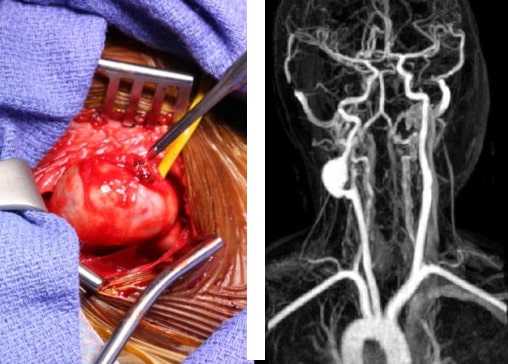

Самым лучшим способом избавиться от патологии и предупредить развитие опасных для жизни осложнений является операция, во время которой патологическую часть отсекают от кровотока.

- Полное удаление опухоли, на месте которой устанавливают протез. Это позволяет восстановить просвет сонной артерии полностью. Если размер пораженного участка превышает 50 мм, проводят его полное удаление с последующей имплантацией резиновых трубок.

- Частичная резекция аневризмы. Проводится в тех случаях, когда невозможно полностью вырезать опухоль. Если операцию провести невозможно по каким-либо показаниям, проводят шунтирование для дальнейшей циркуляции крови.

- Эндоваскулярные методы. Проводят при наличии аневризм маленького размера, располагающихся там, где невозможно традиционное вмешательство. Операцию проводят внутри сосуда, используя специальный катетер. Применяя ангиохирургическую оптику, проводят удаление пораженного сегмента с последующей его заменой протезом.

Если же есть риск осложнений — применяют хирургическое лечение. Оперативное вмешательство влечет за собой резекцию той части сонной артерии, которая связана с аневризмой, и замену удалённого участка трансплантатом.

Еще одним вариантом хирургического лечения является постановка эндоваскулярного стента. Операция проводится в зависимости от размера аневризмы и ее местоположения относительно остальных ветвей сонной артерии. Хирург проходит через прокол в бедренной артерии, используя катетеры для направления и доставки стент-трансплантата в место аневризмы. Рентгеновское наведение используется для размещения трансплантата из искусственного материала в область выпячиваемой стенки сосуда. Затем стент расширяется внутри артерии и удерживается на месте металлическими крючками, а не швами. Преимущество данной методики лечения заключается в снижении операционного риска и сокращении сроков реабилитации пациента.

Основной метод лечения каротидных аневризм на шее - это открытая операция резекции аневризмы с протезированием. Смысл вмешательства заключается в аккуратном выделении аневризматического мешка без повреждения окружающих нервов и сосудов. После тщательного выделения на держалки берётся внутренняя, общая и наружная сонные артерии, расширенный участок сосуда удаляется и протезируется искусственным сосудом или собственной веной пациента. Если кровоток из наружной сонной артерии хороший, то она может быть перевязана.

Эндоваскулярное лечение подразумевает имплантацию специального протеза стент-графта через прокол на шее. Этот протез размещается внутри сонной артерии и изолирует аневризматический мешок от кровотока, благодаря чему полость аневризмы закрывается. При эндоваскулярном лечении значительно снижается риск потери крови и повреждения соседних с сонной артерией нервов и органов шеи.